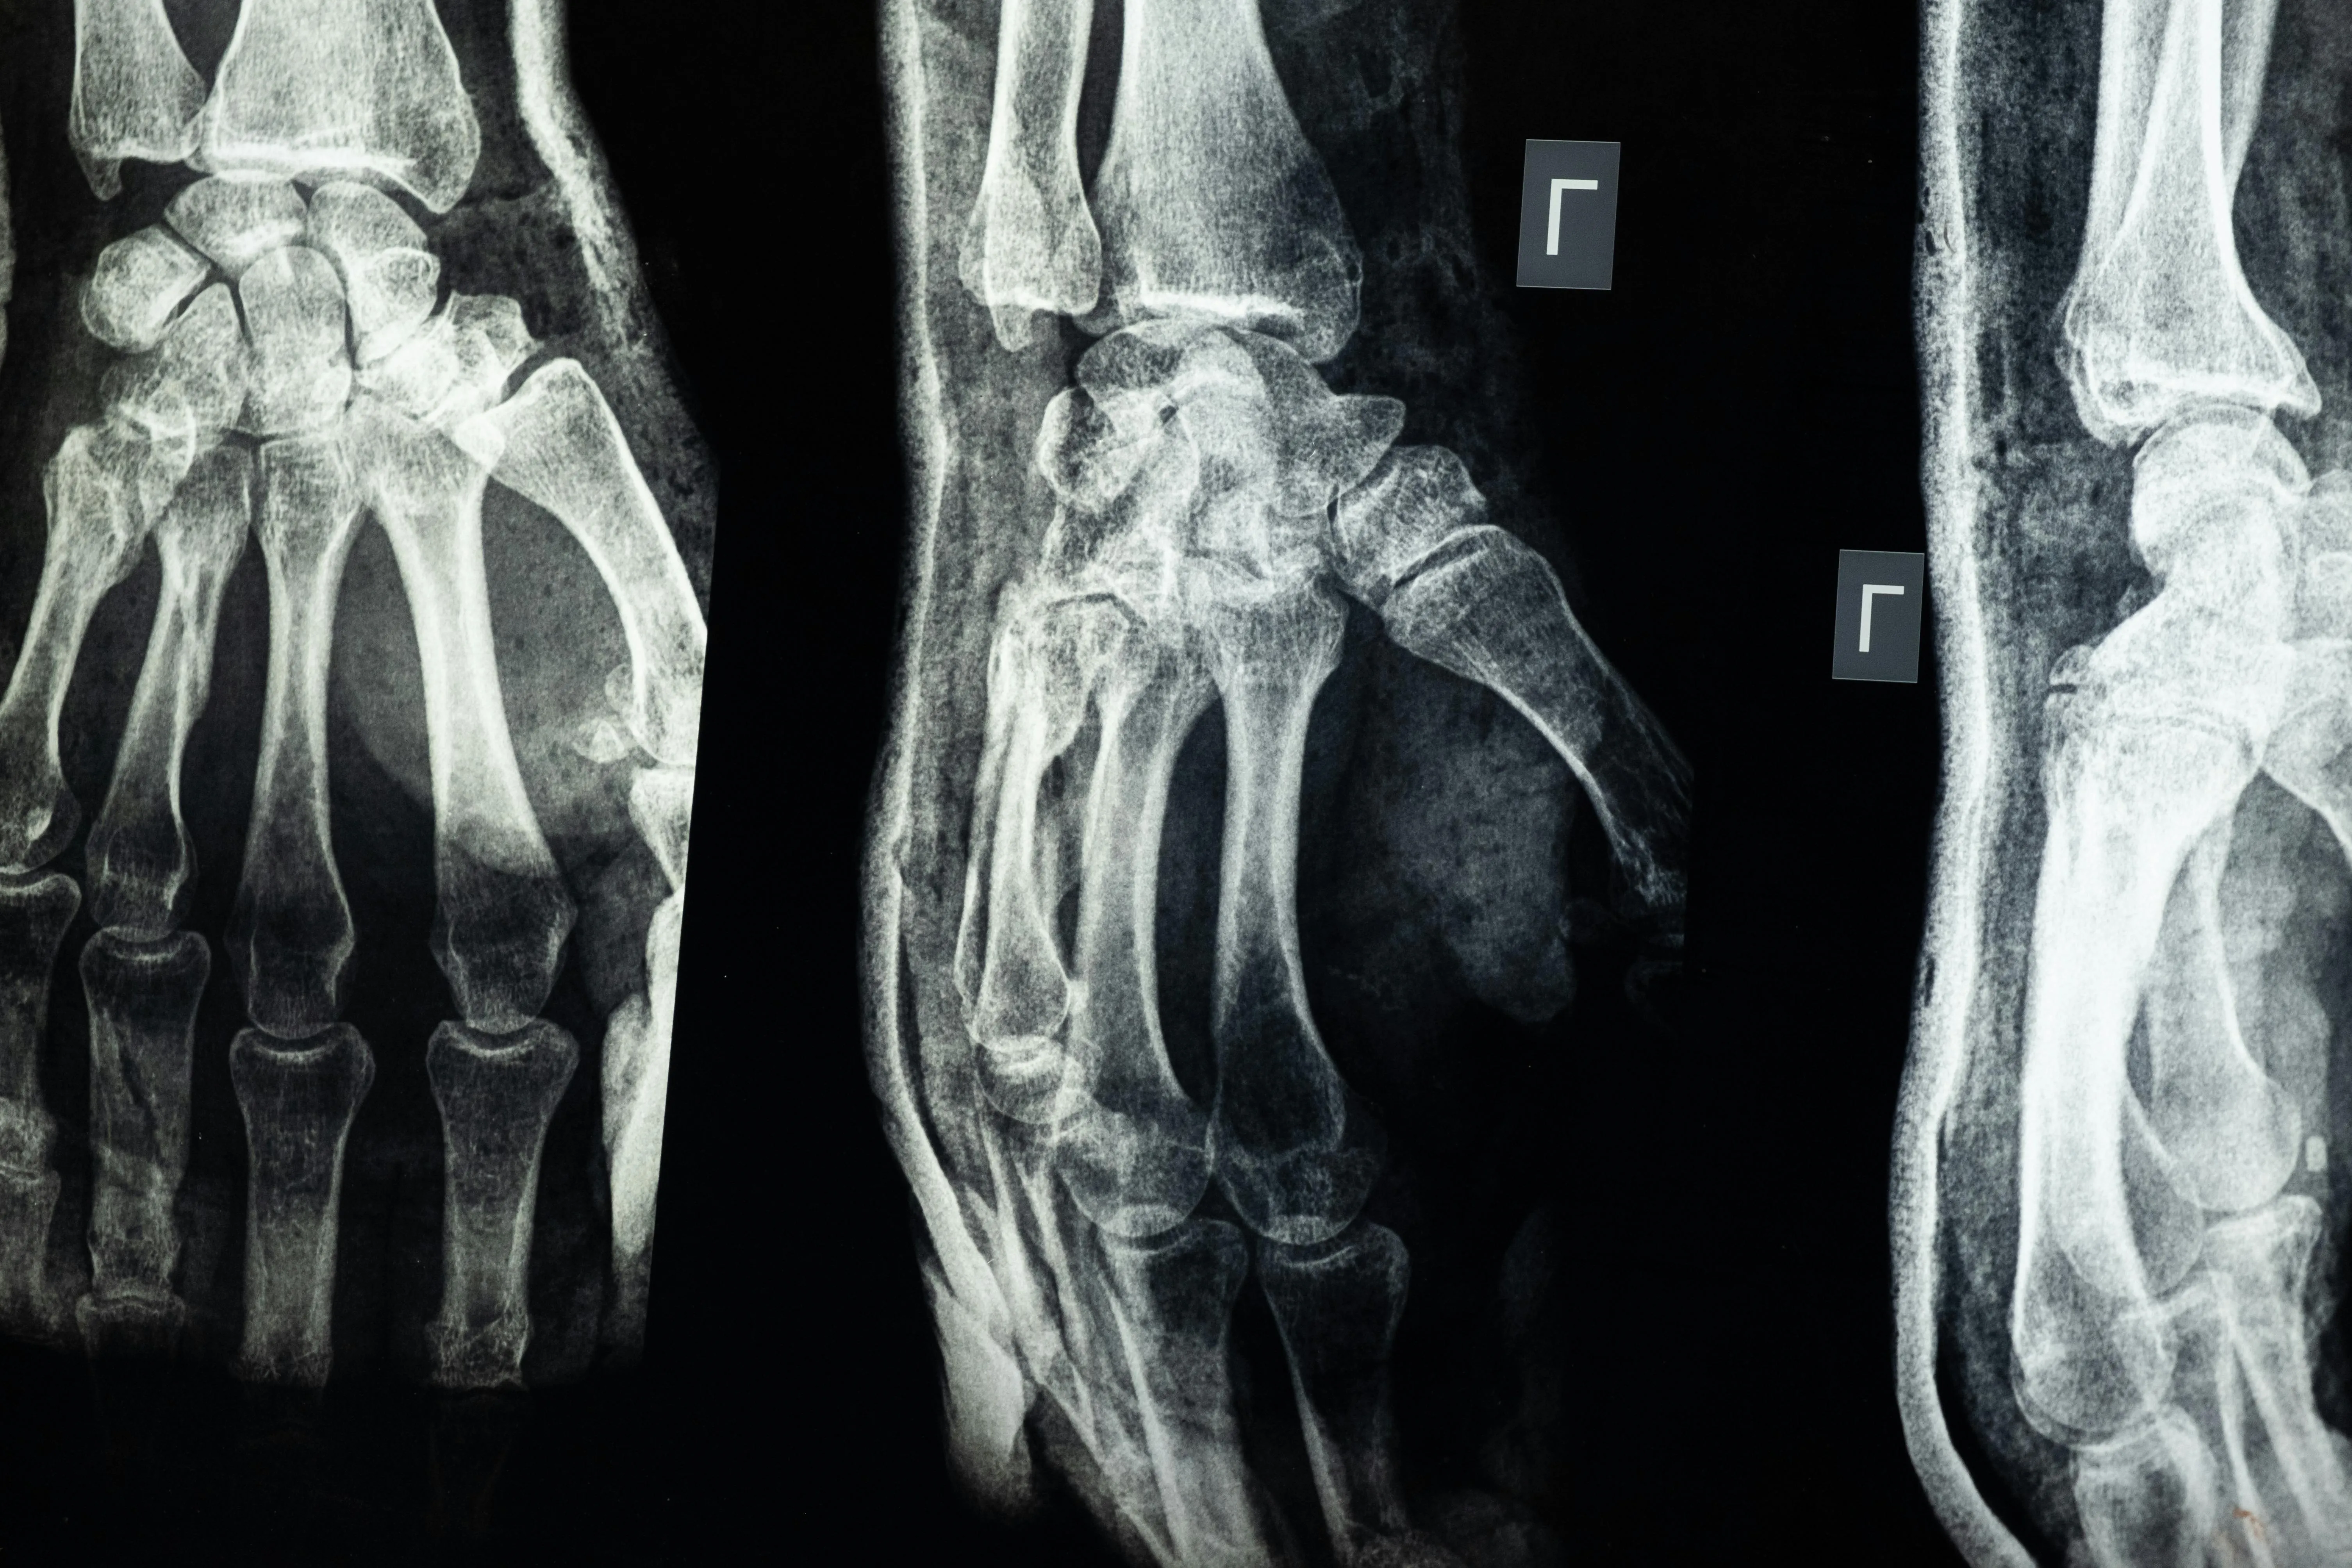

콘드로이친(Chondroitin)은 우리 몸의 연골과 결합조직 속에 자연적으로 존재하는 성분으로

관절 사이에서 충격을 흡수하고 마찰을 줄여주는 역할을 합니다.

나이가 들면서 콘드로이친이 점점 감소하면 관절이 뻣뻣해지고 통증이 생길 수 있다고 합니다.

콘드로이친 효능 2 – 연골 보호 및 재생 도움

콘드로이친은 단순히 통증을 완화하는 것에 그치지 않고,

-연골 세포의 손상을 줄이고 재생을 돕는 역할도 합니다.-

콘드로이친 효능 3 – 관절 윤활 및 유연성 개선

콘드로이친은 관절 속의 윤활 작용을 촉진해 마찰을 줄여주는 역할을 합니다.

실제로 콘드로이친은 관절액의 점도를 높여 유연성을 개선하는 효과가 있다고 합니다.